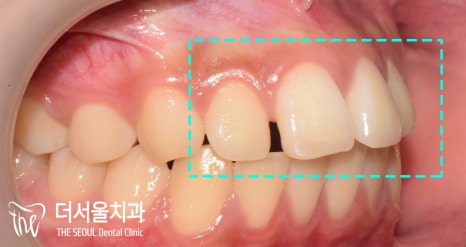

이와 더불어 톡 튀어나와 있는

토끼 이빨이 관찰되고 있는데요.

측면 세팔로 사진에서 볼 수 있듯이

돌출감이 꽤 느껴지고 있었습니다.